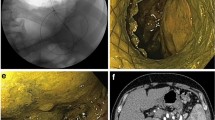

Tumor staging and intraductal involvement were evaluated using computed tomography (CT) and endoscopic ultrasound in all patients. Intraductal ultrasonography was attempted in cases in which intraductal extension diagnosis by endoscopic ultrasound was difficult. Cases with adenoma diagnosed by a preoperative biopsy examination, without bile/pancreatic duct extension, were indicated for EP. PD was recommended for cases diagnosed as carcinoma by preoperative biopsy or adenomas with bile duct/pancreatic duct extension by endoscopic ultrasound/Intraductal ultrasonography; however, EP was performed for cases in which PD was not feasible due to poor general condition, old age, or comorbid disease when T2 invasion was not detected by preoperative imaging studies.

Endoscopic and surgical procedures, pathological diagnosis, and follow up

EP was performed with a standard polypectomy snare using a blended electrosurgical current. Although piecemeal resection was performed, because of their size, the tumors were completely endoscopically resected in all cases. We attempted to insert both the bile duct and pancreatic duct stent after EP. Patients remained hospitalized until a duodenoscopy was performed 7 days after EP; if no bleeding or residual tumor was identified, the stent was removed. The first follow-up duodenoscopy after discharge was scheduled for three months after EP. Follow-up esophagogastroduodenoscopy/CT was scheduled every year for 5 years. If a recurrent lesion was diagnosed as adenoma on biopsy, endoscopic treatment, such as argon plasma coagulation (APC) or additional EP, was performed. PD was recommended for all cases of recurrent carcinoma, but patients who refused or were unfit for PD were treated endoscopically.